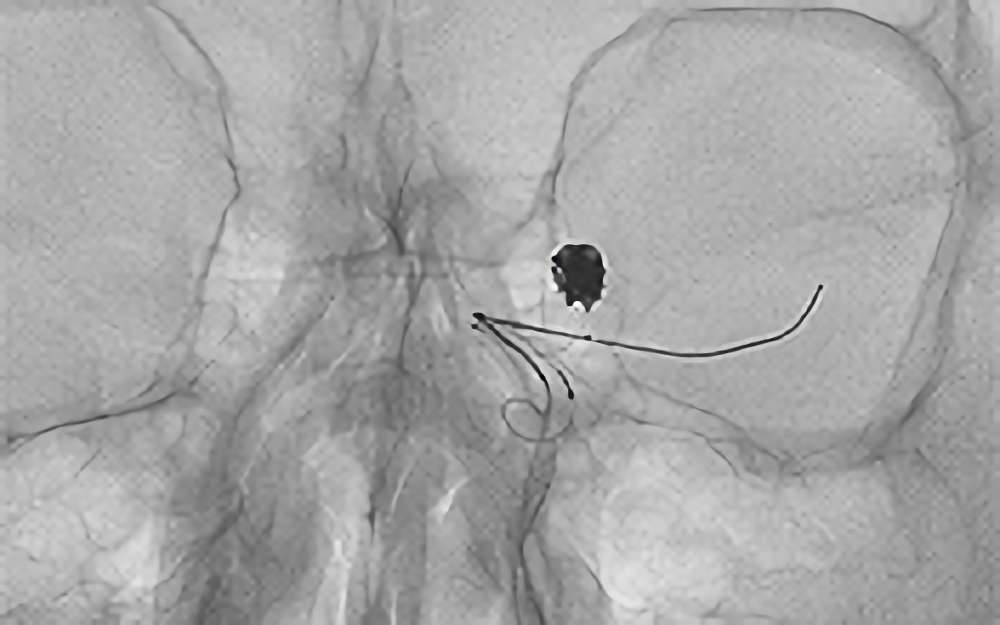

No.1631 手術中